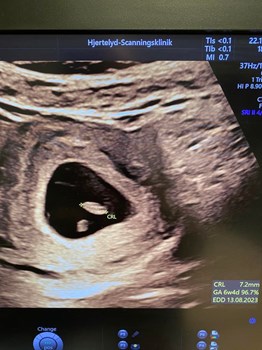

Se hele opslaget på Erhvervsakademi Midtvests FacebooksideSkal du til tidlig scanning i graviditetens første trimester ?? Der er meget stor forskel på bare få uger. Billede 1 er 7. uge ( 6+4) et fint lille fosteranlæg på 7 mm, hjertet slår ca 130 slag i mi...

Se hele opslaget på Hjertelyd - scanningsklinik for gravides FacebooksideKarla bliver gjort klar til laparoskopisk sterilisation 👩🏼⚕️🩺 🐕🦺 Laparoskopisk kirurgi betyder kirurgi i bughulen med kikkert. Ved laparoskopisk sterilisation fjernes ovarierne/æggestokkene, d...